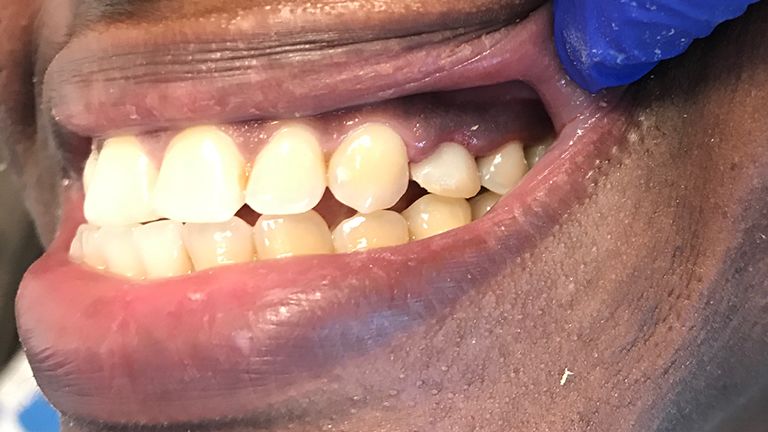

Below is a few examples of what DENTAL IMPLANTS can do for you and your smile!